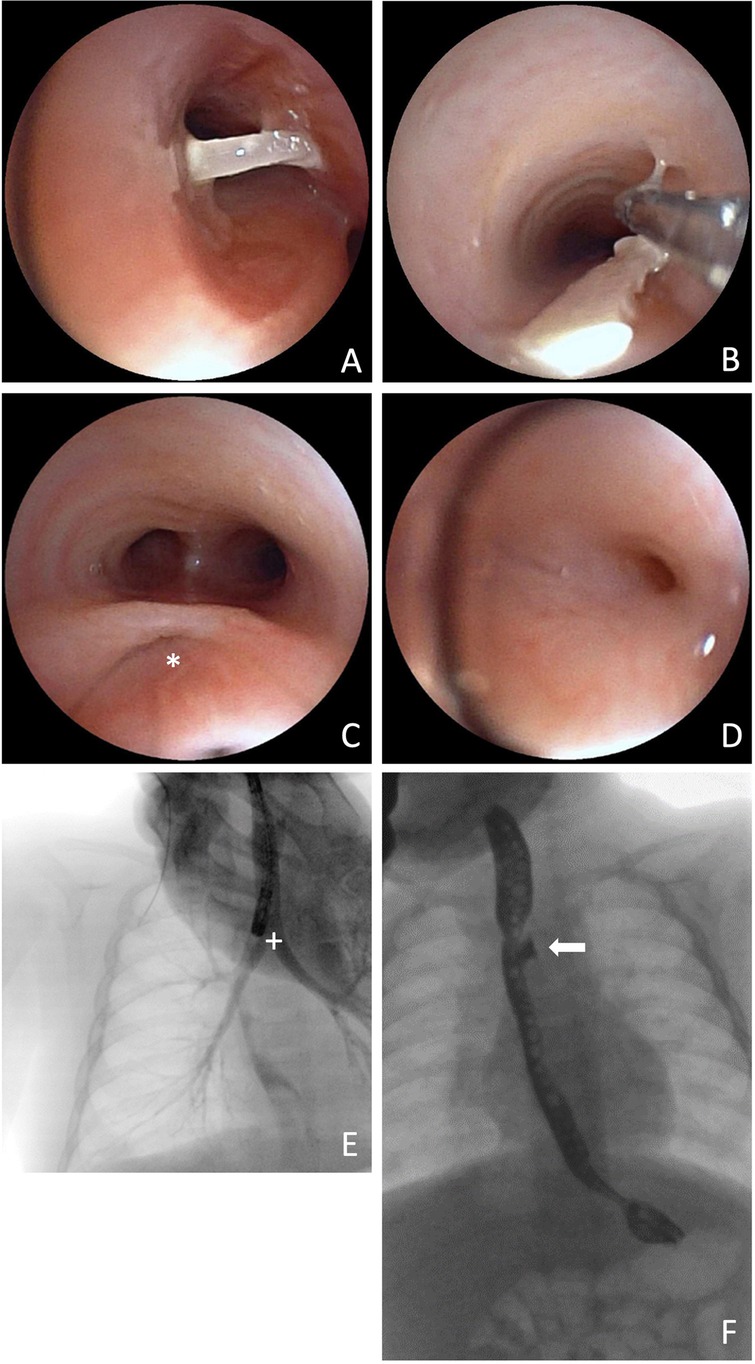

However, the follow-up esophagogastroduodenoscopy, originally planned for six weeks postoperatively, was postponed due to an acute respiratory infection in order to minimize anesthesia-related risks. It was subsequently performed ten weeks postoperatively. At that time, the patient presented with recurrent episodes of bronchitis and exhibited frequent coughing episodes during breastfeeding. Physical examination revealed coarse rattling sounds that resolved after a few forceful tracheal coughs. A flexible bronchoscopy was performed, revealing migration of the polymer clip—originally used for fistula closure—into the right main bronchus. The clip was successfully retrieved using forceps (Figures 3A–B). The residual fistula tract was probed into the mediastinum but not into the esophagus. As a result, endoscopic closure was not performed during this session, and a follow-up bronchoscopy was scheduled for eight weeks later. In the bronchoscopy moderate signs of bronchitis as well as mucosal edema were observed. Cytological analysis of fluid obtained in the bronchoalveolar lavage showed evidence of increased immune cell infiltration. Subsequent esophageal endoscopy revealed an anastomotic stricture, necessitating balloon dilation to restore esophageal patency.

Figure 3. Bronchoscopic view of the clip in the right main bronchus (A) and its extraction via forceps (B), 73 days after initial surgery. Bronchoscopic view of the fistula pouch with ostium (*) (C) and re-fistula ostium at the bottom of the fistula pouch (D). Thoracic x-ray after administration of contrast medium directly into the fistula pouch and contrasted bronchial system (+) (E). Barium swallow examination with contrasted fistula pouch (arrow) (F).

Two months after endoscopic removal of the migrated clip, follow-up bronchoscopy showed no evidence of a re-fistula. The former fistula pouch displayed a small ostium, which, however could not be probed, and no contrast medium passage into the mediastinum was observed even after direct application into the former fistula pouch. Despite this, the patient continued to experience food-associated coughing. At five months postoperatively, an esophageal barium swallow study was performed, revealing a recurrent TEF (Figure 3F). Subsequent bronchoscopy confirmed the diagnosis (Figures 3C–E). Endoscopic chemocauterization of the fistula was performed using a safety swab soaked in 50% trichloroacetic acid applied into the fistula pouch three times for 30s each, followed by fibrin glue application (Figure 4). Immediately the food-associated coughing resolved.